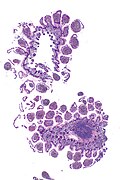

Small bowel pseudomelanosis. H&E stain.

• Dark pigment in the lamina propria macrophages.

Images

Case 1